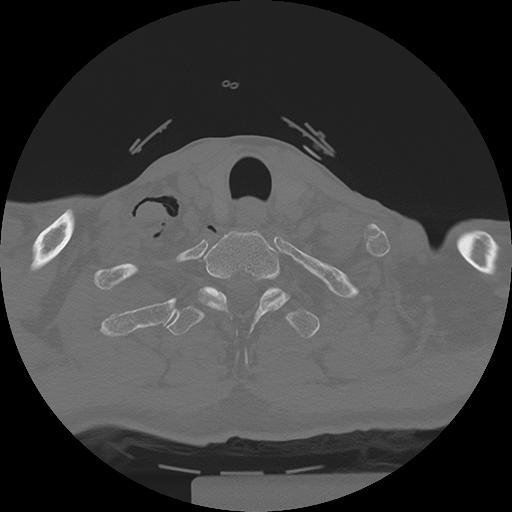

11 HUESO,,Axial,2.0,HUESO,,